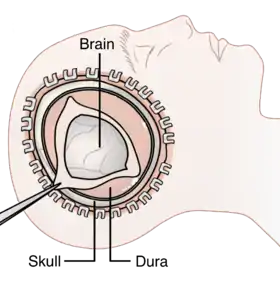

Decompression craniectomy is a procedure commonly used to alleviate the pressure in the brain by removing the pooling blood caused by the ischemic stroke during the perinatal stage.[50] The surgeons will first remove the skin and tissues on top of the site of injury, revealing the skull.[51] Then, a small hole will be made on the skull to allow them to stop the bleeding, before sealing it later.